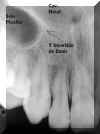

Anatomia

1  2